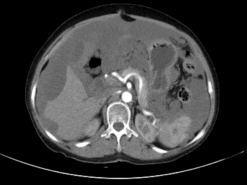

另一位 80 岁老年女性患者因精神萎靡、低热就诊,腹部 CT 检查发现其腹腔积液分布颇具特征:肝脏边缘呈「扇贝形」受压,大网膜增厚呈「饼状」。外院治疗效果不佳,遂至郑大五附院求诊。